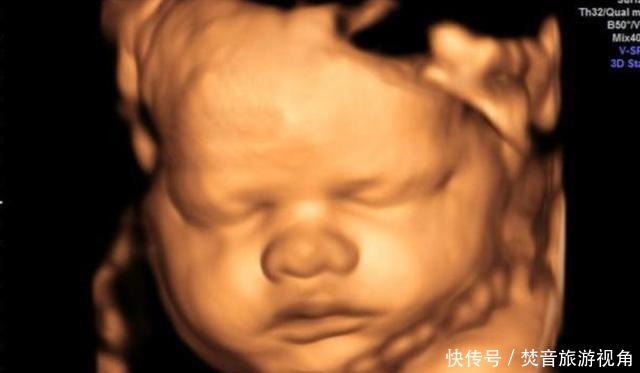

陈女士今年三十三岁,孩子刚刚出生,她非常的开心。别看她如今很坦然,在怀孕期间确实万分小心,对吃的都非常的在意,生怕自己一个不在意对胎儿的身体造成危害。在孕中后期的时候,为了排除更多先天畸形等症状,陈女士在医院做了四维检查。

第一次做检查时,胎儿的脸部、身体都看得非常的清楚,让陈女士感到了很大的安慰。值得一提的是,孩子的一只手伸出了一个手指,非常的可爱。让人没想到的是,第二次检查时,孩子的手指伸出了两根,第三次手指变为了三根,最后一次检查,孩子的手指就变成了四根。